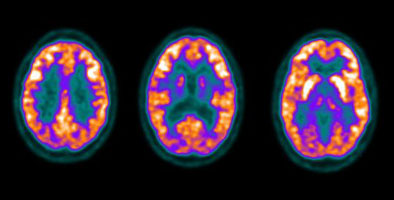

Scott WilliamsHomeCHEST > Tumor > Malignant > Lungcancer > StagingApril 2, 2002HomeCHEST > Tumor > Malignant > Lungcancer > StagingApril 2, 2002HomeCHEST > Tumor > Malignant > Lungcancer > StagingApril 2, 2002HomeNucMed > PET > PET tumor imaging > GeneralApril 2, 2002PETPET > PET tumor imaging > GeneralApril 2, 2002PETPET > PET tumor imaging > GeneralApril 2, 2002PETPET > PET tumor imaging > GeneralApril 2, 2002CardiacCardiac > Adultdz > Atrial FibrillationApril 2, 2002RIARIAApril 2, 2002RIARIAApril 2, 2002Previous PagePage 33 of 265Next PageTop StoriesMolecular ImagingPET predicts faster cognitive decline in women than menWomen initially outperformed men at low brain tau levels, but the advantage diminished as tau levels increased over time.MRIUnclear explanations of contrast MRI exams heighten patient anxietyWomens ImagingMammography screening improves survival for late-stage cancersUltrasoundUltrasound MinnieCast, Episode 2: Body imaging with RUS-PATSponsor ContentHow Agentic AI Is Transforming Radiology Ops